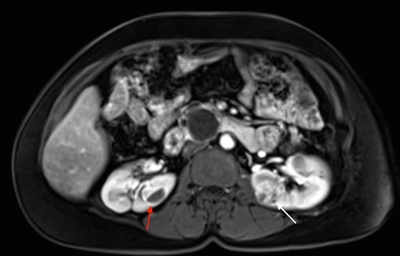

Más del 55 % de las personas con la enfermedad de Von Hippel-Lindau (VHL) solo presentan múltiples quistes de células renales. Los carcinomas de células renales (RCC) relacionados con la enfermedad de VHL suelen ser multifocales y bilaterales, y forman masas con componentes quísticos y sólidos.[1] En la enfermedad de VHL, se notificó un riesgo acumulado de RCC del 24 % al 45 %. Los RCC menores de 3 cm tienden a ser de grado bajo (grado nuclear de Fuhrman 2) y de invasión mínima.[2] Sin embargo, su tasa de crecimiento varía mucho.[3] En una investigación de 228 lesiones renales en 28 pacientes seguidos durante por lo menos 1 año, se observó que la transición de un quiste simple a una lesión sólida fue infrecuente.[1] Los quistes complejos y las lesiones sólidas contenían tejido neoplásico uniformemente extendido. Estos datos se pueden usar para predecir la progresión de las lesiones renales (de benignas a malignas) en pacientes con enfermedad de VHL. En la Figura 1 se observan tumores renales bilaterales en un paciente con enfermedad de VHL.